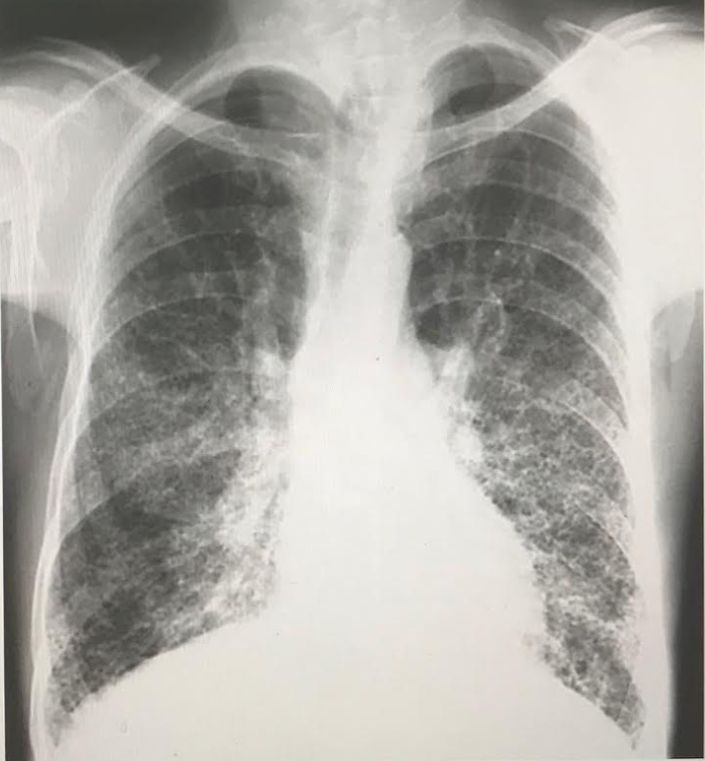

The following CXR is highly suggestive of what restrictive pulmonary pathology in a ~ 50 year old man? _____